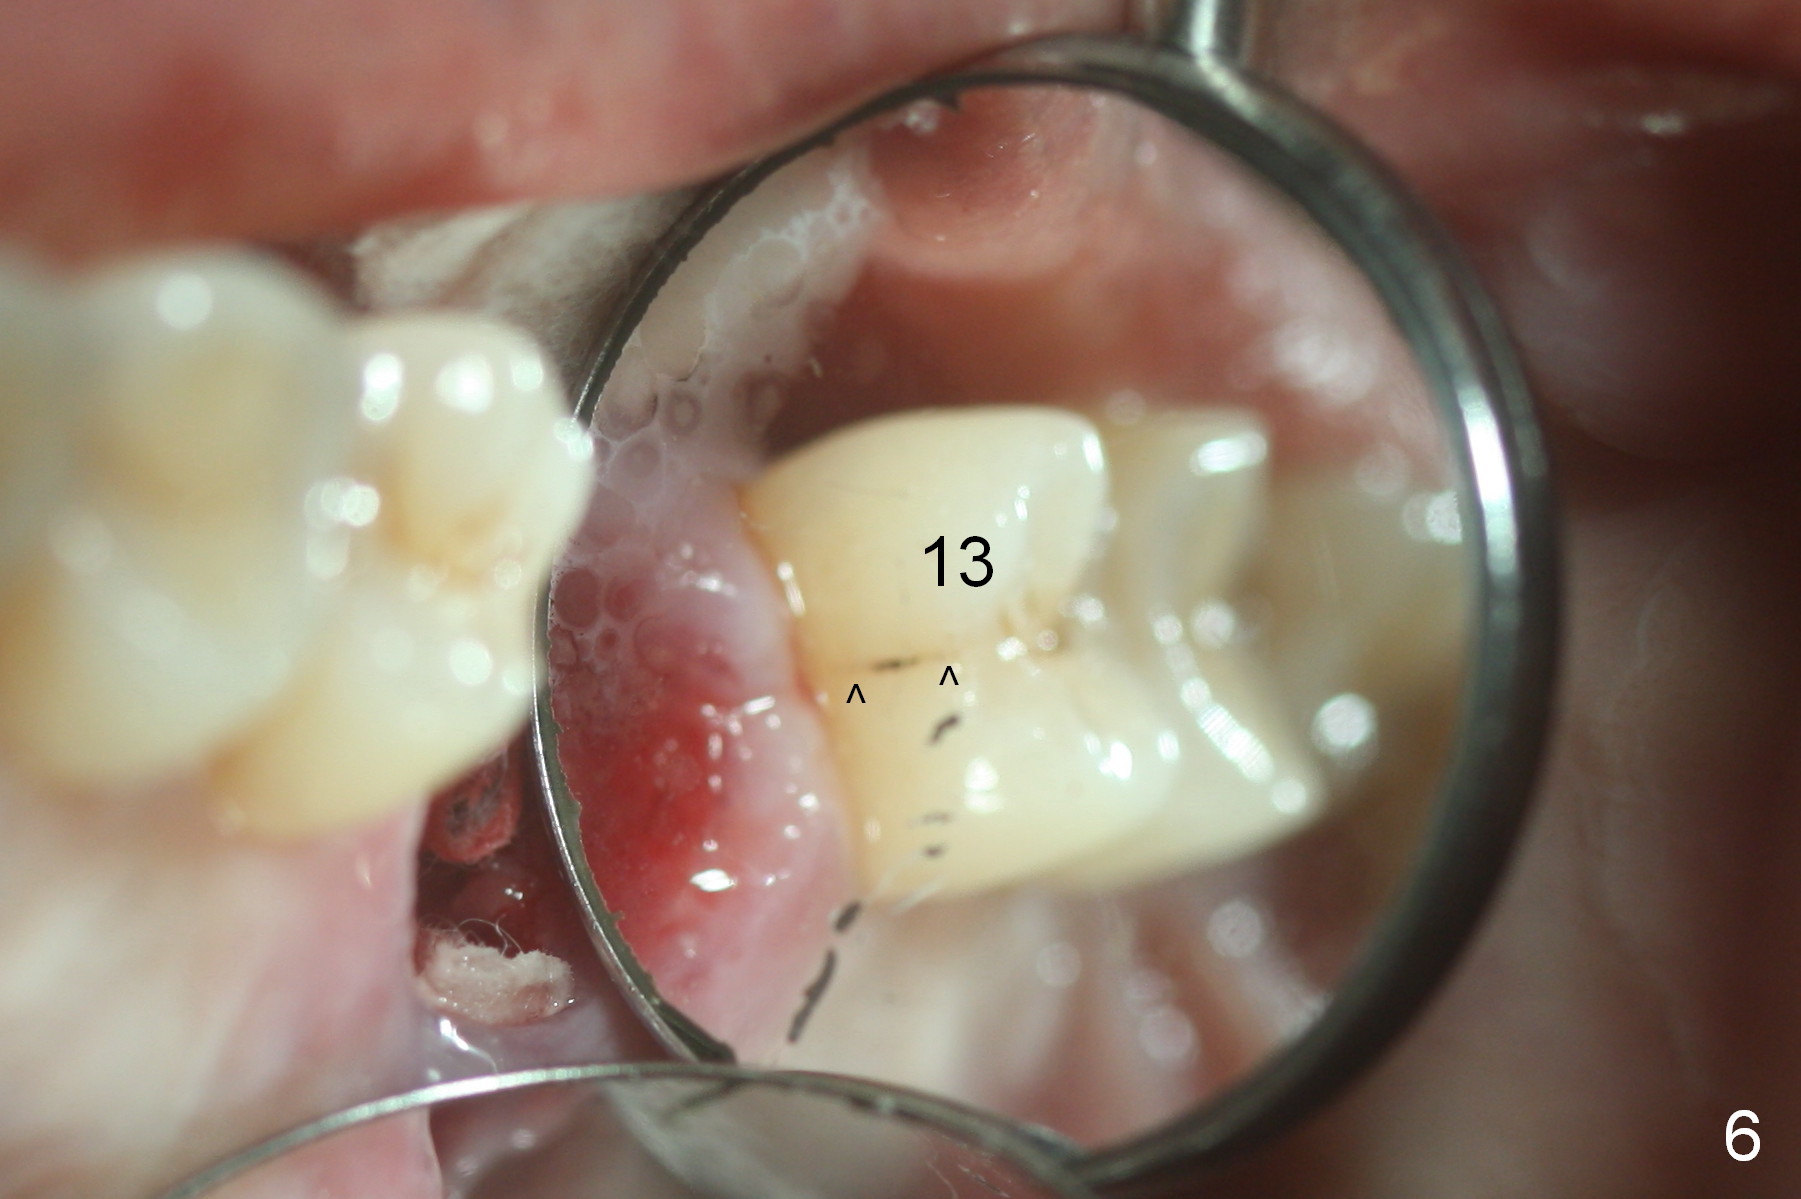

When the tooth is extracted, the lingual crack line (Fig.4 white <) is contiguous with the mesiobuccal one (black >). The latter corresponds to the white arrowheads in Fig.2. In all the crack line is extensive. The buccal and palatal plates are defective coronally. The large granulation tissue in the furca (Fig.5 *) suggests bone loss in the crestal septum. Most surprising is a crack line in the distal surface of the tooth #13 (Fig.6 ^) and in the mesial surface of #15 (Fig.7). Night guard will be fabricated after an implant crown is cemented at #14.